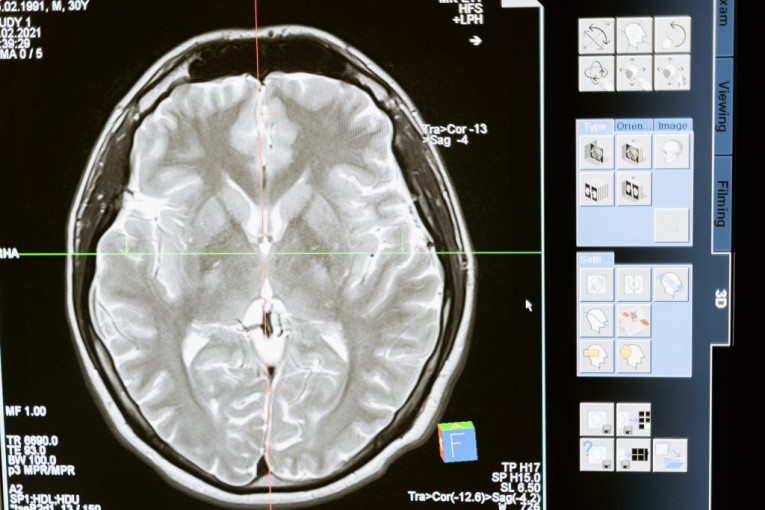

Život posle smrti postoji, bar onaj biološki, pošto pojedine ćelije ljudskog mozga ostaju aktivne nekoliko sati nakon što čovek umre, tvrde naučnici u novoj studiji.

Radi se o glijalnim ćelijama, pratećim ćelijama u ljudskom mozgu koje ne spadaju u neuronske, već koriste za ishranu, zaštitu i potporu neuronima i oko njih obrazuju mijelinski omotač.

Ovakve karakteristike glijalnih ćelija, zbog kojih su dobile nadimak "zombi" ćelije, otkrio je tim na čijem čelu je bio Džefri Leb, šef odseka za neurologiju na čikaškom Medicinskom koledžu Univerziteta Ilinois.

- Većina studija pretpostavlja da se u mozgu sve zaustavlja kada srce prestane da kuca, ali to nije slučaj. Naši nalazi će biti neophodni kako bi se tumačila istraživanja ljudskih moždanih tkiva, pošto ovakve promene na glijalnim ćelijama do sada nisu bile precizno ustanovljene - kaže on.

Foto: pexels.com- Glijalne ćelije su inflamatorne i njihov zadatak je da „počiste“ okolinu posle oštećenja mozga, kao što su nedostatak kiseonika ili moždani udar - kaže Leb.

Ovakvi rezultati istraživanja mogli bi da budu veoma značajni u drugim studijama koje izučavaju uzorke mozga, jer naučnici, koji se bave istraživanjem neuroloških oboljenja, do sada nisu uzimali u obzir posmrtnu aktivnost glijalnih ćelija. Drugim rečima, istraživanja neuroloških oboljenja sada će biti znatno preciznija, navodi RT.

Ali čak ni "zombi" ćelije ne žive zauvek. Istraživanje naučnika koje je predvodio Džefri Leb utvrdilo je da su glijalne ćelije aktivne 24 sata posle smrti, a da se posle toga ne mogu razlikovati od moždanog tkiva koje počinje da se raspada.